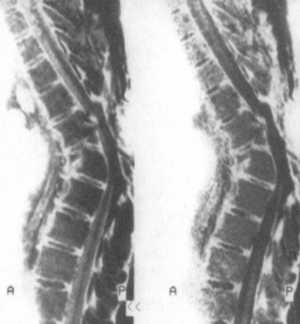

Рис. 12.1. МРТ-исследование грудного

Атрофия спинного мозга лучше всего визуализируется в сагиттальной проекции

на T1BИ, а в аксиальной - хорошо отражается как на T1BИ, так и на Т2ВИ (рис.

12.1). Структура МР-сигнала бывает неоднородной за счет глиозных и микро-кистозных

изменений в спинном мозге, его интенсивность изменяется соответственно тем

или иным процессам. Так, микрокистозные изменения на T1BИ проявляются снижением

интенсивности МР-сигнала, а на T2BИ повышением до уровня сигнала спинномозговой

жидкости (СМЖ) или его превышением.